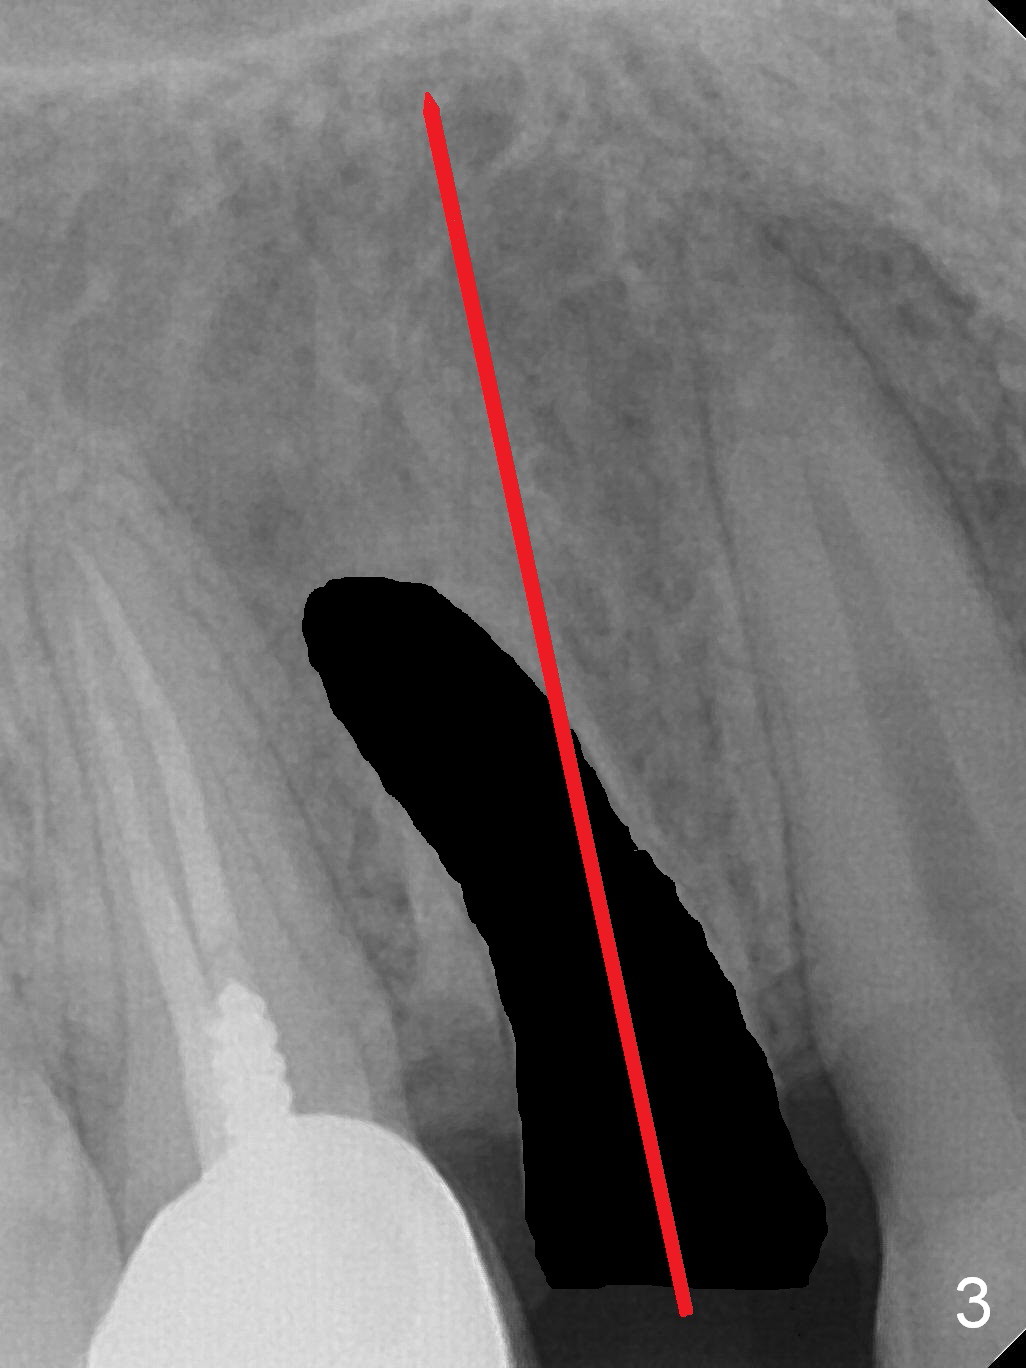

A 34-year-old man (smoker, half a pack a day) has residual root at #5 (Fig.1) with large periapical radiolucency (Fig.2 red dashed line).  Since the root curves distally (Fig.3 black area, Clindamycin), osteotomy will be established in the mesial wall (red long arrow).  A 3.8x16 or 18 mm implant is to be placed for primary stability (Fig.4).  To reduce periimplantitis associated with smoking, place the implant deep.  The implant appears to have better surface treatment.  Pack sufficient bone graft and membrane.  Immediate provisional should have good seal.  To place the implant deep, osteotomy will be attempted with a long 1.5 mm pilot drill (PA), followed by 2 mm one with extension and 3.0x18 mm drill.